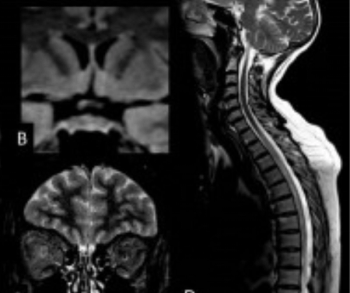

Utilizing susceptibility-weighted magnetic resonance imaging (MRI) in a study involving over 20,700 people, researchers found that drinking more than seven units (56 grams) of alcohol a week led to a higher accumulation of brain iron, which can trigger cognitive decline.